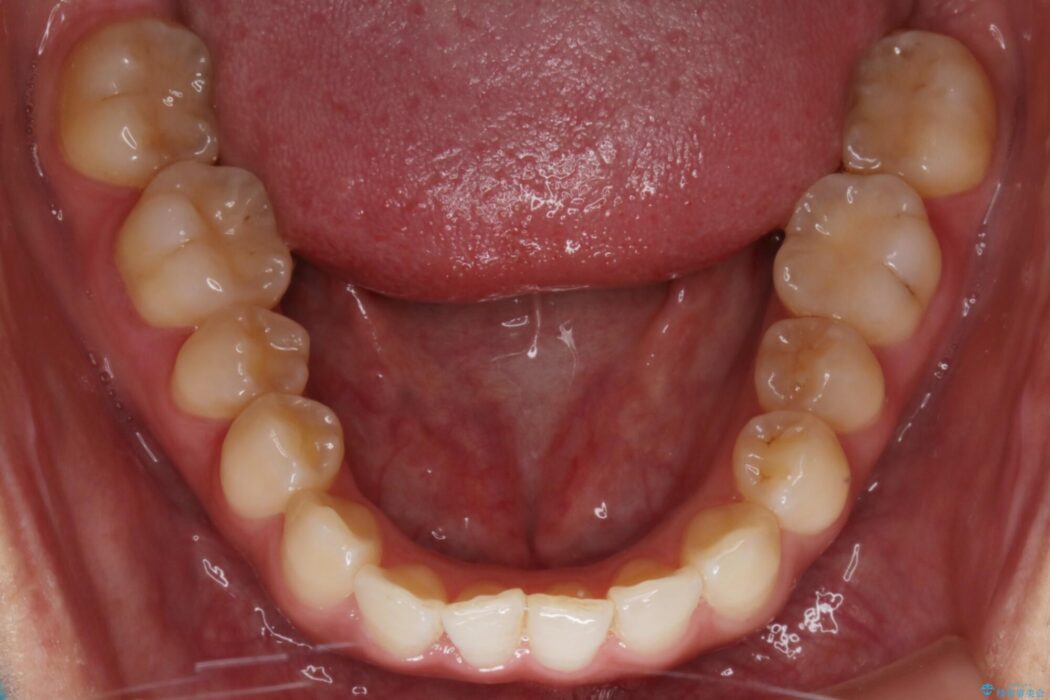

【20代女性】軽度の反対咬合を部分矯正でなおす

治療後について

反対咬合の歯も整ったアーチに収まり、きれいに仕上がりました。

今回のケースでは前歯部の軽い凹凸のみであったため部分矯正の適応範囲に該当していました。

適応例は限られますが、部分矯正は全体矯正と比べると矯正期間が短く、費用も安く済みます。